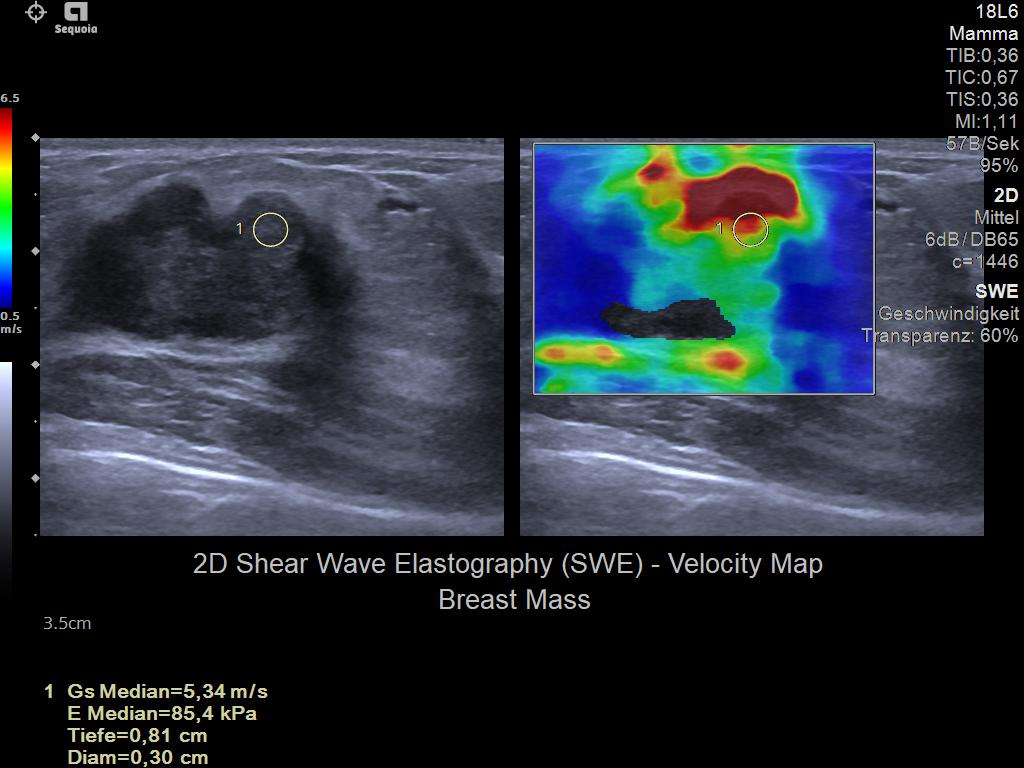

- Next Gen 2D-SWE for greater sensitivity in detection and visualization of malignant breast lesions.